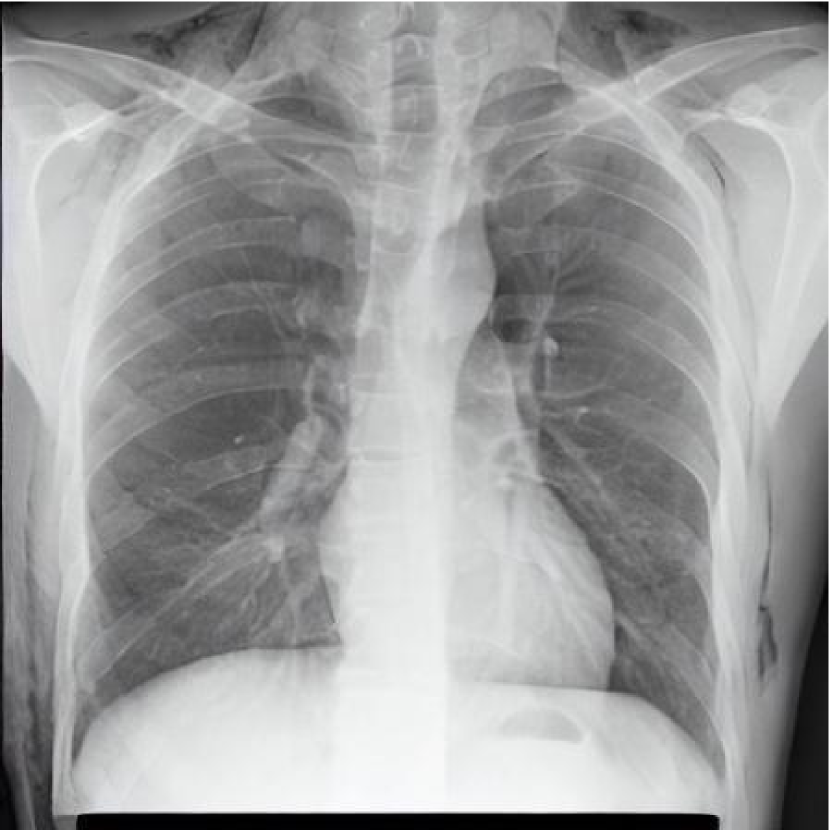

Leveraging Synthetic Data. With the advent of generative modelling tools, we are armed with the power to mitigate the problem of having a long-tail by supplementing the rare labels. We run a small experiment to evaluate whether we can use RoentGen [2], a prompt-based Stable Diffusion model to generate realistic chest X-rays and augment the training data. We generate about 5000 X-rays for training containing at least one pathology from the tail classes. We curate prompts for RoentGen by translating the Spanish reports available in the PadChest dataset to English, and also generate radiologist report-like prompts using ChatGPT 111chat.openai.com by providing curated templates. Figure 3 shows examples of prompts and the corresponding synthetic X-rays generated by RoentGen and verified by a radiologist.

Contribution of Synthetic Data. Figure 2 shows the increase in performance of the model over Table 1. This model was jointly finetuned on MIMIC CXR and a small synthetic dataset (refer Figure 3 for samples). Although the size of the synthetic dataset was too small for it to demonstrate an appreciable performance delta, these results show the promise of leveraging synthetic data to overcome the challenge of training on rare classes at least to some extent, especially since the biggest change is seen in the performance of the tail classes.